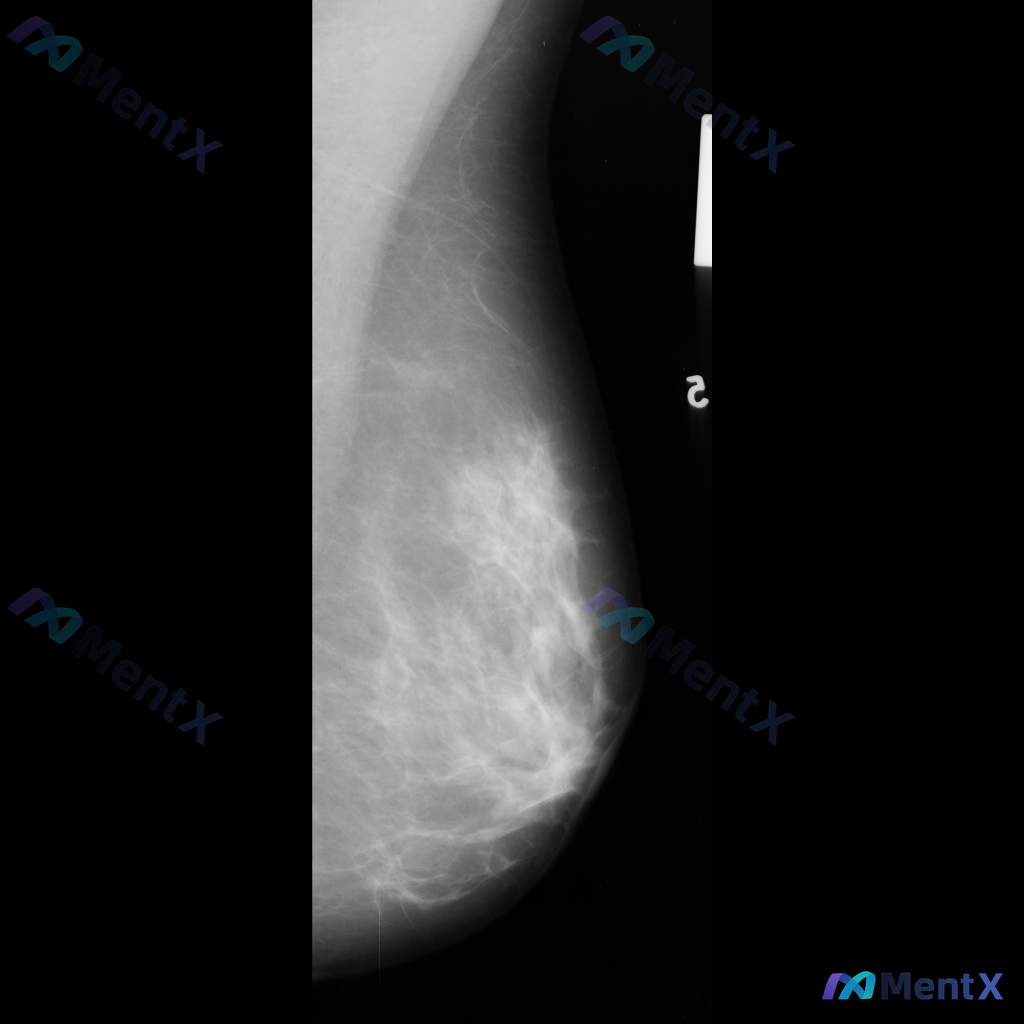

整理到一份乳腺影像的分析资料,想请大家一起讨论看看。 基本信息: - 影像类型:左侧乳腺钼靶内外斜位(MLO) 影像主要表现: 1. 左侧乳腺中上部及外侧可见局灶性结构扭曲 2. 乳腺腺体组织以纤维腺体为主,密度较高,为不均匀致密型(ACR BI-RADS C型) 3. 腺体可见多发斑片状、结节状高...